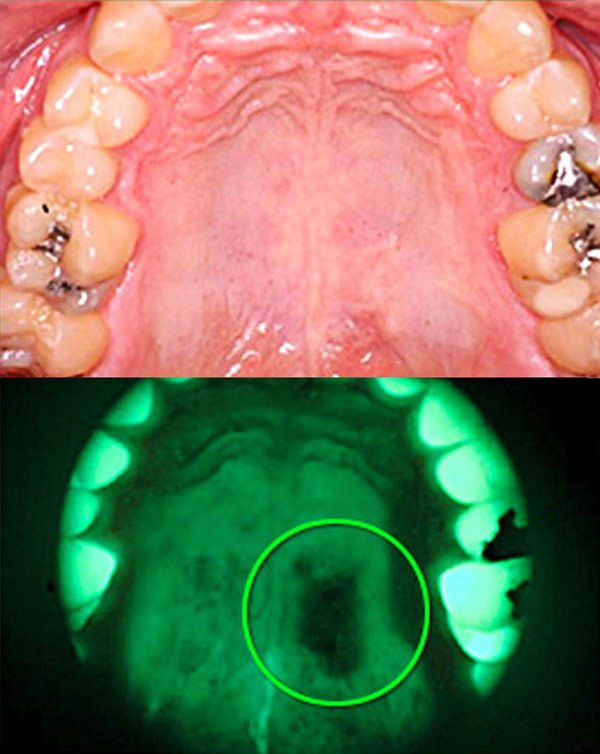

VELScope VELScope

Szájüregi rákszűrés Szájüregi rákszűrés

Gyanús elváltozás Gyanús elváltozás

A VELscope rendszer biztonságos, látható kék fényt bocsát ki, amely gerjeszti a nyálkahártya szöveteit és fluoreszkál. A fogorvos megvizsgálhatja a lágy szöveteket és azonosíthatja a gyanús elváltozásokat. Az egészséges szövetek jellemzően élénkzöld fényként jelennek meg, míg a gyanús elváltozások a fluoreszcencia hiányát okozzák, és sötét színűnek tűnnek.